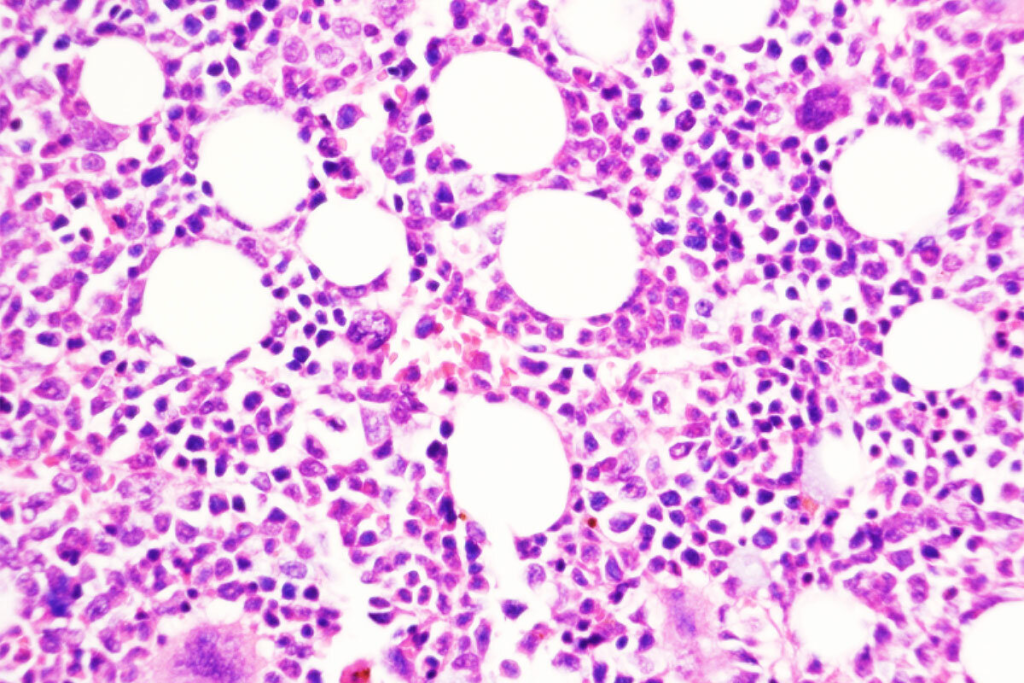

Bone Marrow Examination

Bone marrow tests are very important for diagnosing blood disorders. We take a sample of bone marrow to check how blood cells are made. This helps us find any problems, like cancer cells.

What we learn from these tests helps us understand why you’re sick. It also guides how we should treat you.

Bone marrow examinations are also vital. They help doctors see how far leukemia has spread. They also figure out the type of leukemia.

- Bone marrow biopsy to assess leukemia cell presence